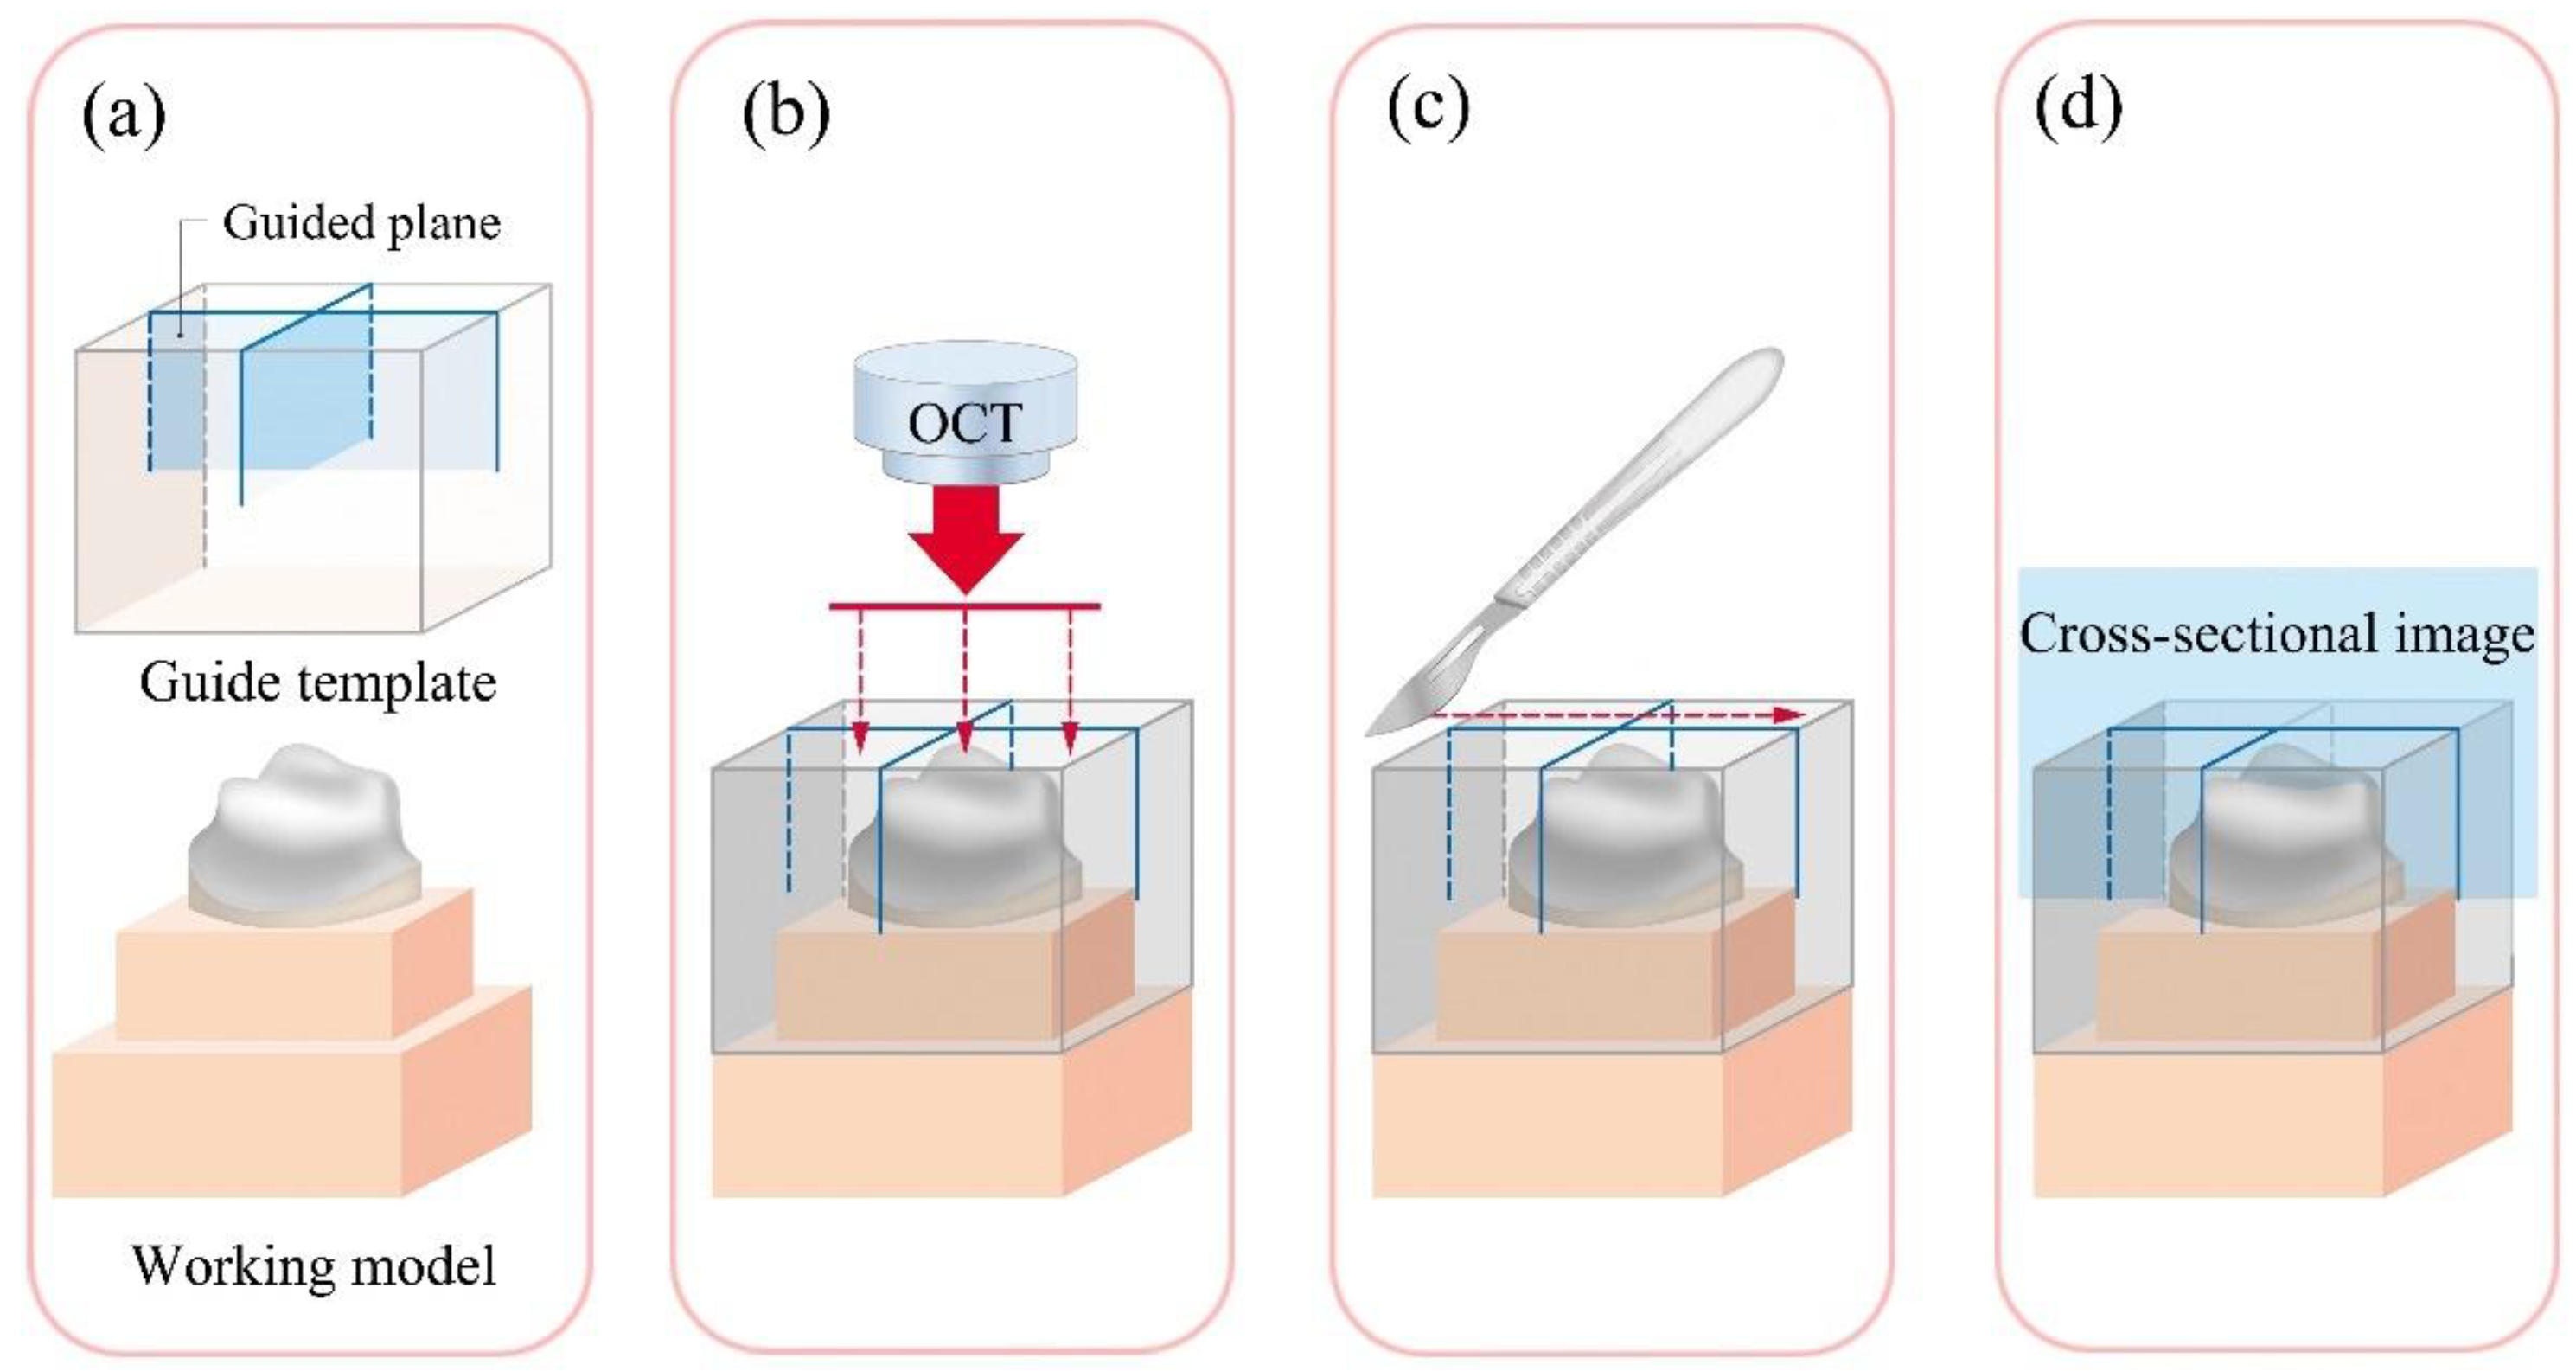

- Optical coherence tomography (OCT): OCT is a method of measurement using higher resolution 2D or 3D images in optical scattering media using coherent light. This is a non-destructive, non-radiological method with the advantage of allowing the acquisition of higher resolution images in real time, which are often utilized for in vivo research [37]. On the other hand, its disadvantage includes difficulty in measuring very thick or optical-opaque materials [16,17,18,19,20,21]. Both 2D and 3D analysis are possible with TSM, MCT, and OCT.

2.2.5. Optical Coherence Tomography (OCT Group)